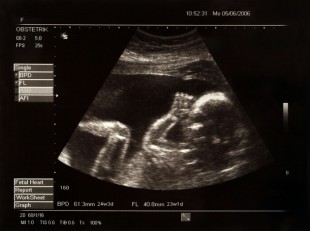

Segundo diretor geral da Maternidade Dona Catarina Kuss, Luiz Mann, a paciente em questão foi encaminhada até a maternidade e as três vezes foi atendida. “Ela foi atendida três vezes, está anotado no prontuário que é de domínio da própria família. Inclusive na quinta-feira, que antecedeu o problema com o futuro bebê, a médica de plantão fez os exames corretamente e apresentou os resultados. Onde mostrava os batimentos do coração do bebê e identificava-se que estava com plena saúde”, explicou Luiz.

Também ao falar do número de óbitos de recém-nascidos, sete mortos em três meses, afirma que este dado está errado, pois não eram recém-nascidos e sim óbitos fetais. “Não é recém-nascidos, bebês. Houve óbitos fetais, que é totalmente diferente para quem conhece sobre área é natimorto (aborto espontâneo), que acontece aos três, seis, sete meses. Por isso digo recém-nascidos é uma coisa, óbito fetal é outra”.

Para explicar ao leitor um natimorto ou aborto espontâneo é uma denominação dada ao feto que morreu dentro do útero ou durante o parto, ou seja, quando ocorre óbito fetal. Óbito fetal é a morte de um produto da concepção ocorrida antes da expulsão ou de sua extração completa do corpo materno, independentemente da duração da gestação. A indicação do óbito fetal é dada pelo fato de que, após a separação do corpo materno, o feto não respire ou mostre qualquer outra evidência de vida, tais como: batimento do coração, pulsação do cordão umbilical ou movimento efetivo dos músculos de contração voluntária.